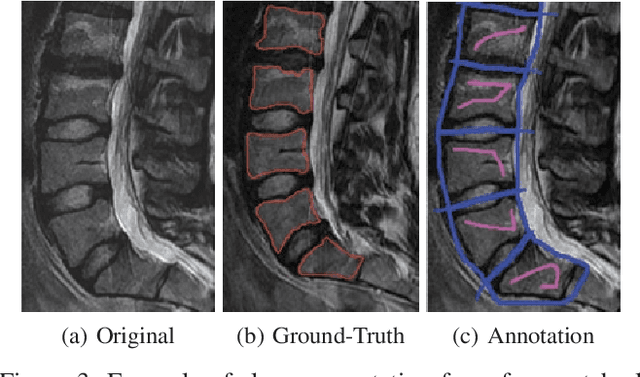

Abstract:Segmentation of medical images is a critical issue: several process of analysis and classification rely on this segmentation. With the growing number of people presenting back pain and problems related to it, the automatic or semi-automatic segmentation of fractured vertebral bodies became a challenging task. In general, those fractures present several regions with non-homogeneous intensities and the dark regions are quite similar to the structures nearby. Aimed at overriding this challenge, in this paper we present a semi-automatic segmentation method, called Balanced Growth (BGrowth). The experimental results on a dataset with 102 crushed and 89 normal vertebrae show that our approach significantly outperforms well-known methods from the literature. We have achieved an accuracy up to 95% while keeping acceptable processing time performance, that is equivalent to the state-of-the-artmethods. Moreover, BGrowth presents the best results even with a rough (sloppy) manual annotation (seed points).